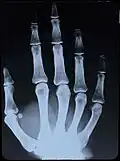

Original: X-Ray image of right hand;

colored 1st. order equidensity-series using pseudo-solarization, B&W copies chromogenic developed